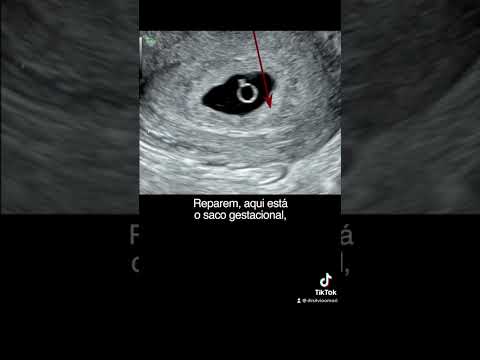

4 SEMANAS | Ultrassom ObstétricoСкачать

6 semanas de gestação | Ultrassom obstétricoСкачать